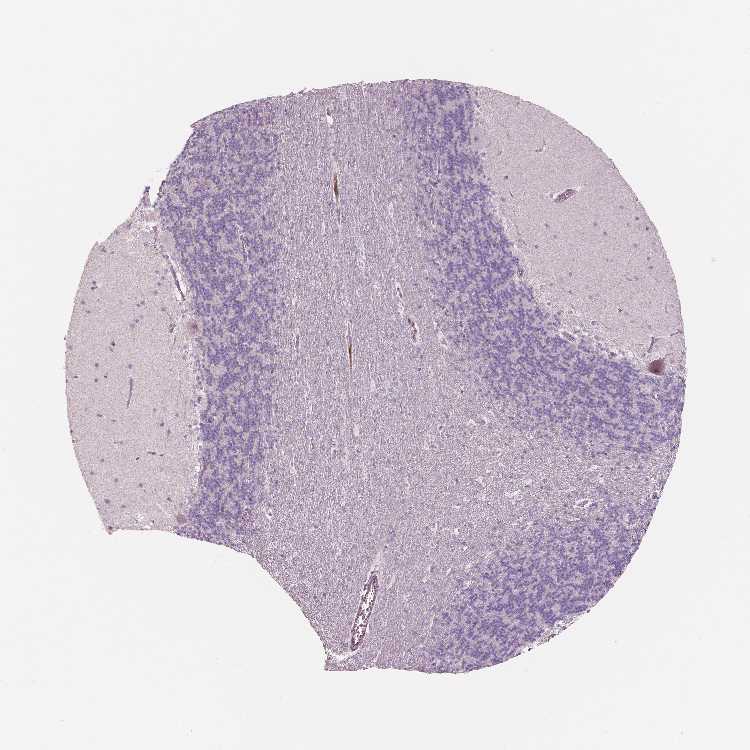

CEREBELLUM - Antibody stainingi

Antibody staining in the annotated cell types in the current human tissue is reported as not detected, low, medium, or high, based on conventional immunohistochemistry profiling in selected tissues. This score is based on the combination of the staining intensity and fraction of stained cells.

Each image is clickable and will lead to virtual microscopy that enables deeper exploration of all samples and also displays staining intensity scores, fraction scores and subcellular localization as well as patient and tissue information for each sample.

Antibody HPA001352Antibody HPA002549Antibody CAB068250Antibody CAB068251Antibody CAB068252

Purkinje cells Not detectedNot detectedNot detectedNot detectedNot detected

Cells in granular layer Not detectedNot detectedNot detectedNot detectedNot detected

Cells in molecular layer Not detectedNot detectedNot detectedNot detectedNot detected